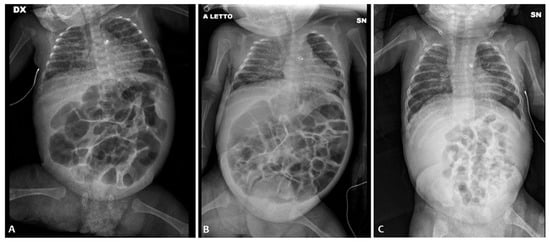

Afterward, on the 4th dol, the baby was intubated again and then transferred to our NICU because of worsening abdominal distension; in the suspicion of intestinal obstruction or NEC, antibiotic treatment was started.

At admission, the belly was distended (Figure 3) and painful on palpation, with bile-stained vomiting. AXR showed no signs of NEC. On the 5th day of life, after a rectal enema with saline solution, a sticky meconium passage was observed. Therefore, NAC rectal enemas were performed daily. On the 8th day of life, NAC was also given by nasogastric tube (three times/day). Enteral feeding was started on the 13th day of life and then transiently stopped because of two septic episodes. Cystic fibrosis and thyroid anomalies were ruled out. Full enteral feeding was reached on the 80th day of life and NAC rectal enemas were stopped.

Figure 3. Abdominal X-ray of patient P3 on the 3rd day of life (A); abdominal X-ray before the NAC treatment (B) and after the NAC treatment (C).